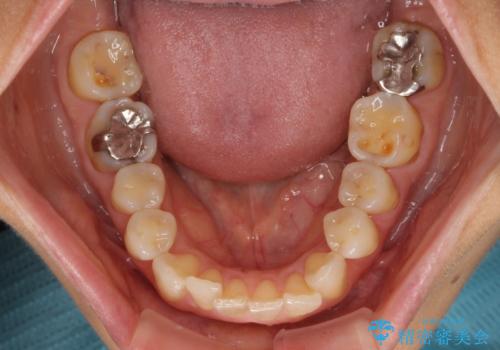

- 奥歯の銀歯をすべてゴールドにすることを希望された患者様です。

セラミックインレーによる補綴治療も提案しましたが、ご自身で強い咬合力を認識しており、歯にもインレーにもダメージの少ないゴールドインレーにて処置することとしました。